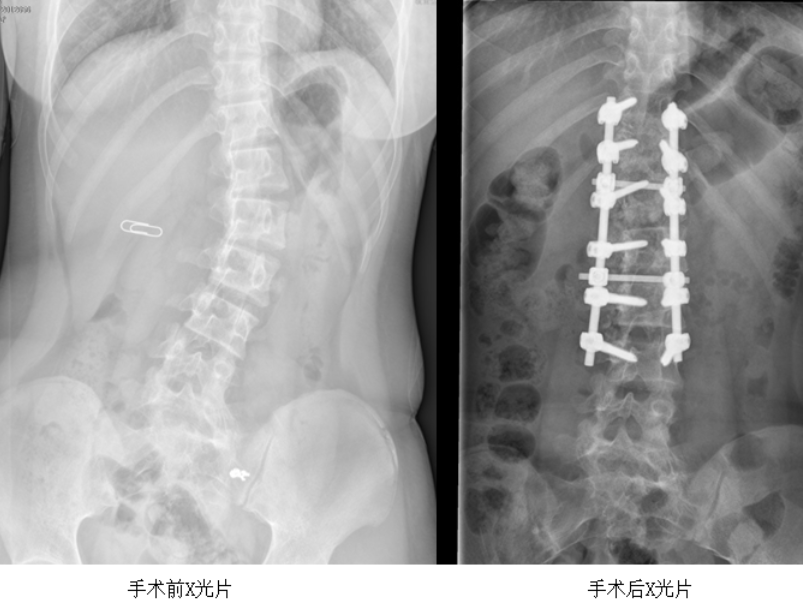

项目服务医院为患者开展脊柱矫正治疗